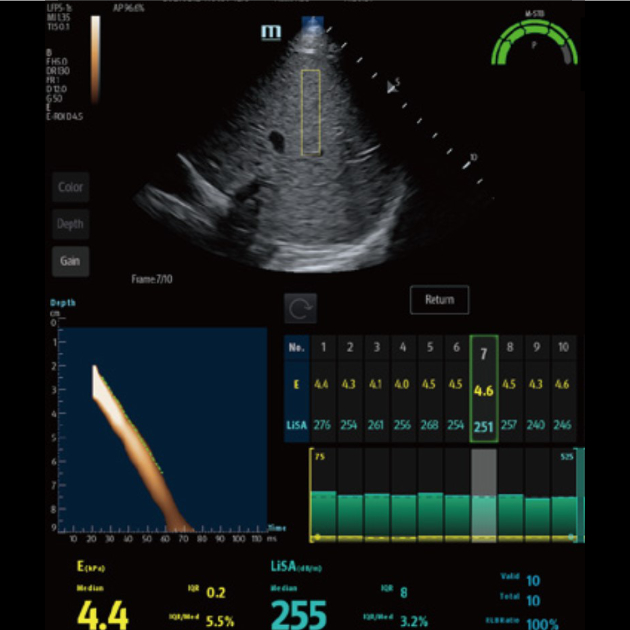

Avancerad ViTE (Visualized Transient Elastography)

- Utför kvantitativ detektion och utvärdering av leverfibros och steatos med visuell vägledning i realtid via 2D-ultraljud.

- Möjliggör undvikande av blodkärl och lesioner, vilket förbättrar mätningens noggrannhet och tillförlitlighet.

- Minskar avsevärt handhavandets komplexitet och ökar precisionen och reproducerbarheten vid kvantitativa mätningar.

- Ultrasnabb mätning – 10 automatiska datainsamlingar på en knapptryckning.

- Tryckindex (P): kvalitetskontroll av probens tryck.

- Rörelsestabilitetsindex (m-STB): säkerställer andningsstabilitet.

- Tydliga färgindikeringar som förbättrar kvalitetskontrollen under undersökningen.

Kvantitativ analys av leverstyvhet

Ger kvantitativ mätning av leverstyvhet och bedömning av graden av leverfibros med hjälp av transient elastografi-teknologi.

Kvantitativ analys av leversteatos

Graden av leversteatos kan kvantitativt utvärderas med LiSA-teknologi (Liver Ultra-Sound Attenuation).